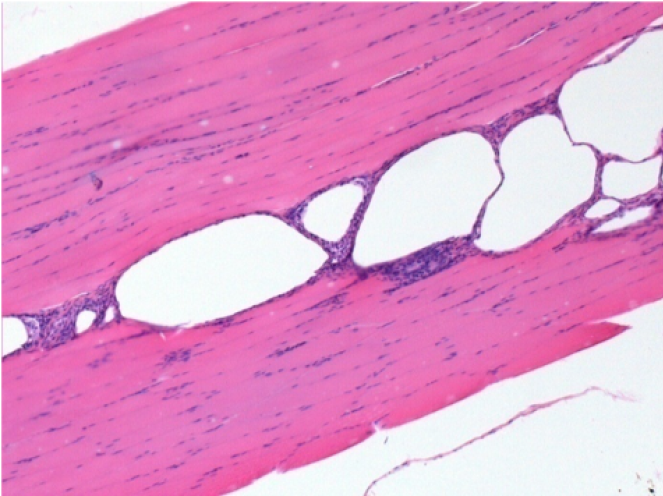

10 giorni dopo iniezione di Endopeel

Scatola Nr 2

- 10 giorni dopo iniezione 0.1ml di Endopeel nel muscolo pretibiale destro (Dx).

- Si osserva formazioni di vacuole , le quali circondate da linfociti.

- Le quali Vacuole sono differenti dal tessuto necrotico.

- La presenza di linfociti é correlata alla permeabilità delle membrane cellulari.

Sx : Controllo-100x-Giorno10

Dx:100x-Giorno10

Dx :200x-Giorno10

Dx :400x - Giorno10